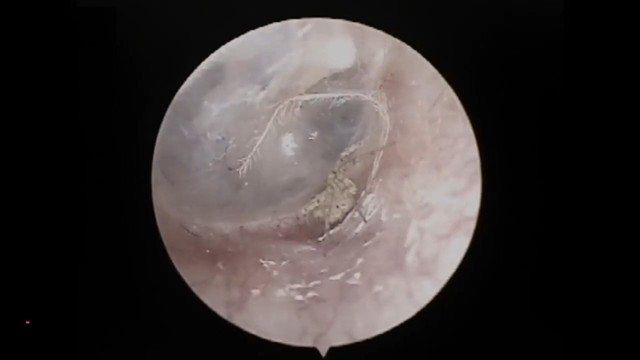

上班途中耳朵痒 蜘蛛爬进去结网

(北京3日综合电)中国江苏省扬州20多岁的上班族小李(化名),日前突然感到耳内极度搔痒,就医后竟然在耳道深处发现一只活蜘蛛正在织网!

《梨视频》报导,小礼当天走路上班时,突然觉得好像有东西进入耳道,到了公司本想自己把异物夹出,但花了约2小时还是没办法,加上耳朵越来越痒,才决定到扬州大学附设医院就医。

负责诊疗的耳鼻喉科医师张攀表示,经过内视镜检查,确认在小李的耳道深处有只活体生物,应该是蜘蛛,且已在小李的耳道内结了网。由于蜘蛛所在的位置太深,已无法使用工具夹出,张攀决定缓缓朝小里耳道内注入生理食盐水,很快就将蜘蛛赶了出来。